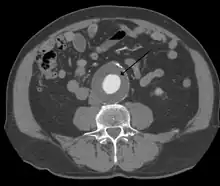

The diagnosis of an abdominal aortic aneurysm can be confirmed by the use of ultrasound. Rupture may be indicated by the presence of free fluid in the abdomen. A contrast-enhanced abdominal CT scan is the best test to diagnose an AAA and guide treatment options.[14]

A large, rapidly expanding, or symptomatic aneurysm should be repaired, as it has a greater chance of rupture. Slowly expanding aortic aneurysms may be followed by routine diagnostic testing (i.e.: CT scan or ultrasound imaging).